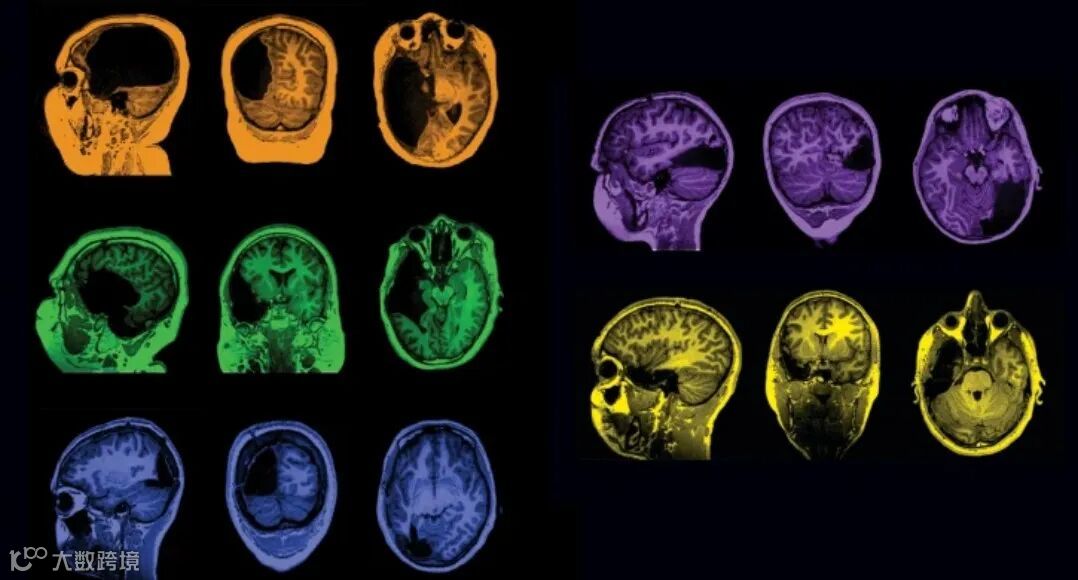

🌟Cross-sectional and longitudinal changes in category selectivity in visual cortex following pediatric cortical resection

- 作者:Liu, T.T., Granovetter, M.C., S. Maallo, A.M. et al.